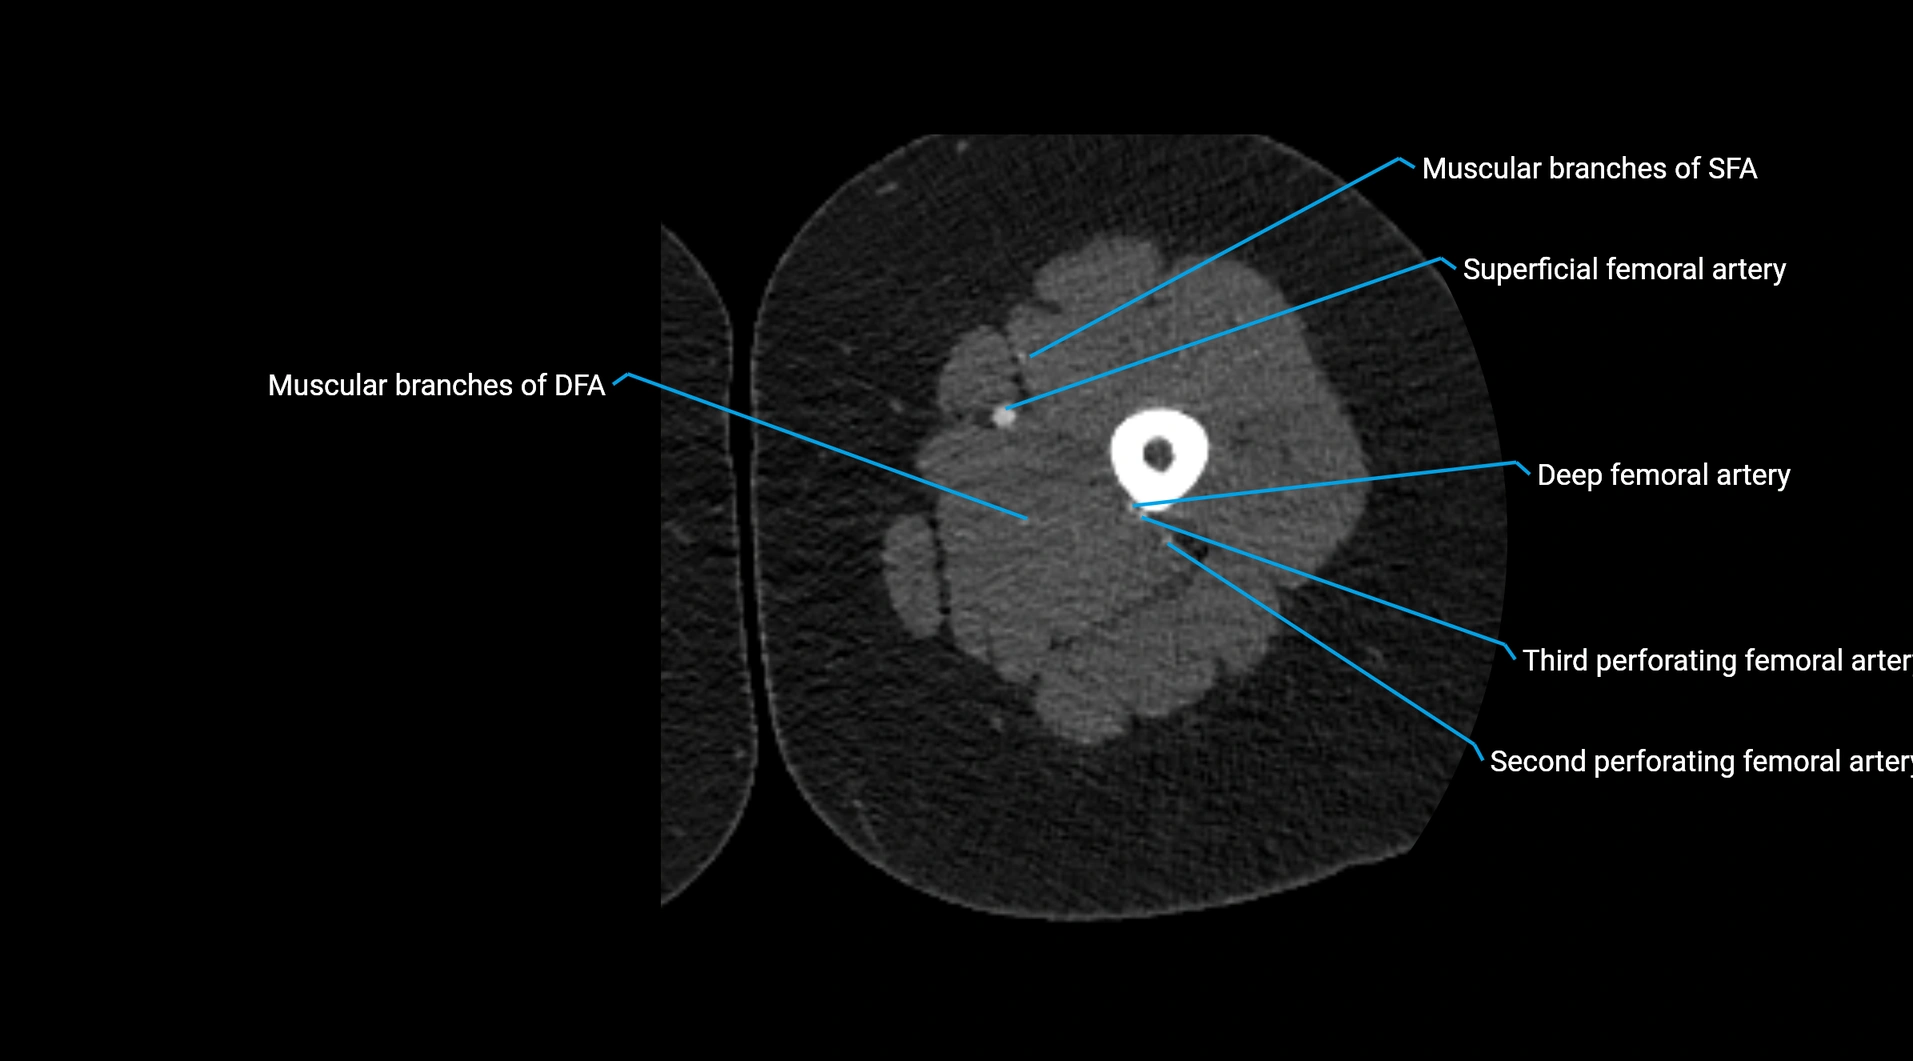

CT images

image

Contrast-enhanced CT (CTA):

• Gold standard for abdominal aortic imaging

• Provides excellent detail of lumen, wall, aneurysm, thrombus, and branch vessels

• Multiplanar and 3D reconstructions help in aneurysm measurement, stent graft planning, and dissection evaluation